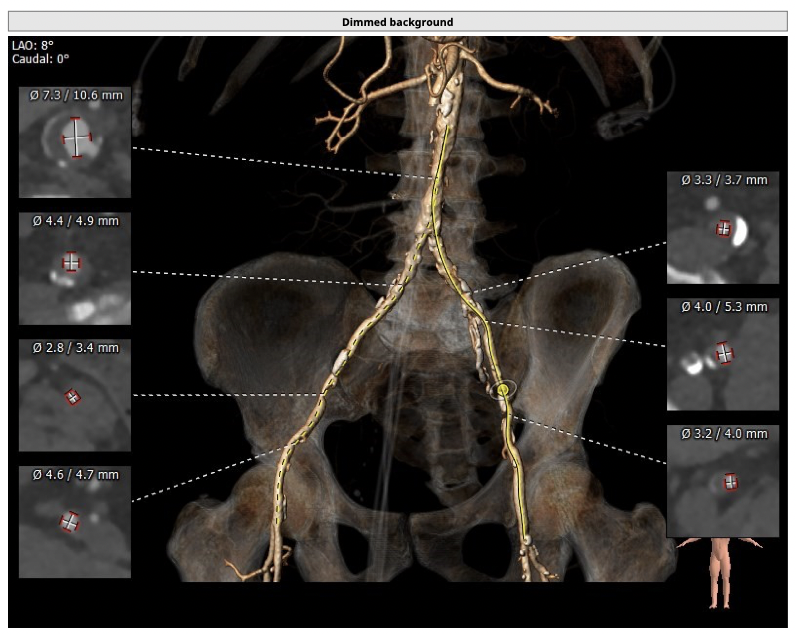

①患者因规律透析导致钙磷代谢紊乱,外周血管斑块钙化严重,最狭窄处仅2.8mm,通路建立难度极大(左右颈动脉均不符合入路条件);

确保冠脉安全,拟采取PCI+TAVR一站式手术策略,因患者右侧股动脉钙化严重、入路狭窄,拟采取无鞘法从右股动脉穿刺入路,选用20mm球囊预扩、L23号VenusA-Valve瓣膜、采用VenusA-Plus输送系统确保瓣膜的精确释放,瓣膜释放后结合造影和超声情况,决定是否后扩。